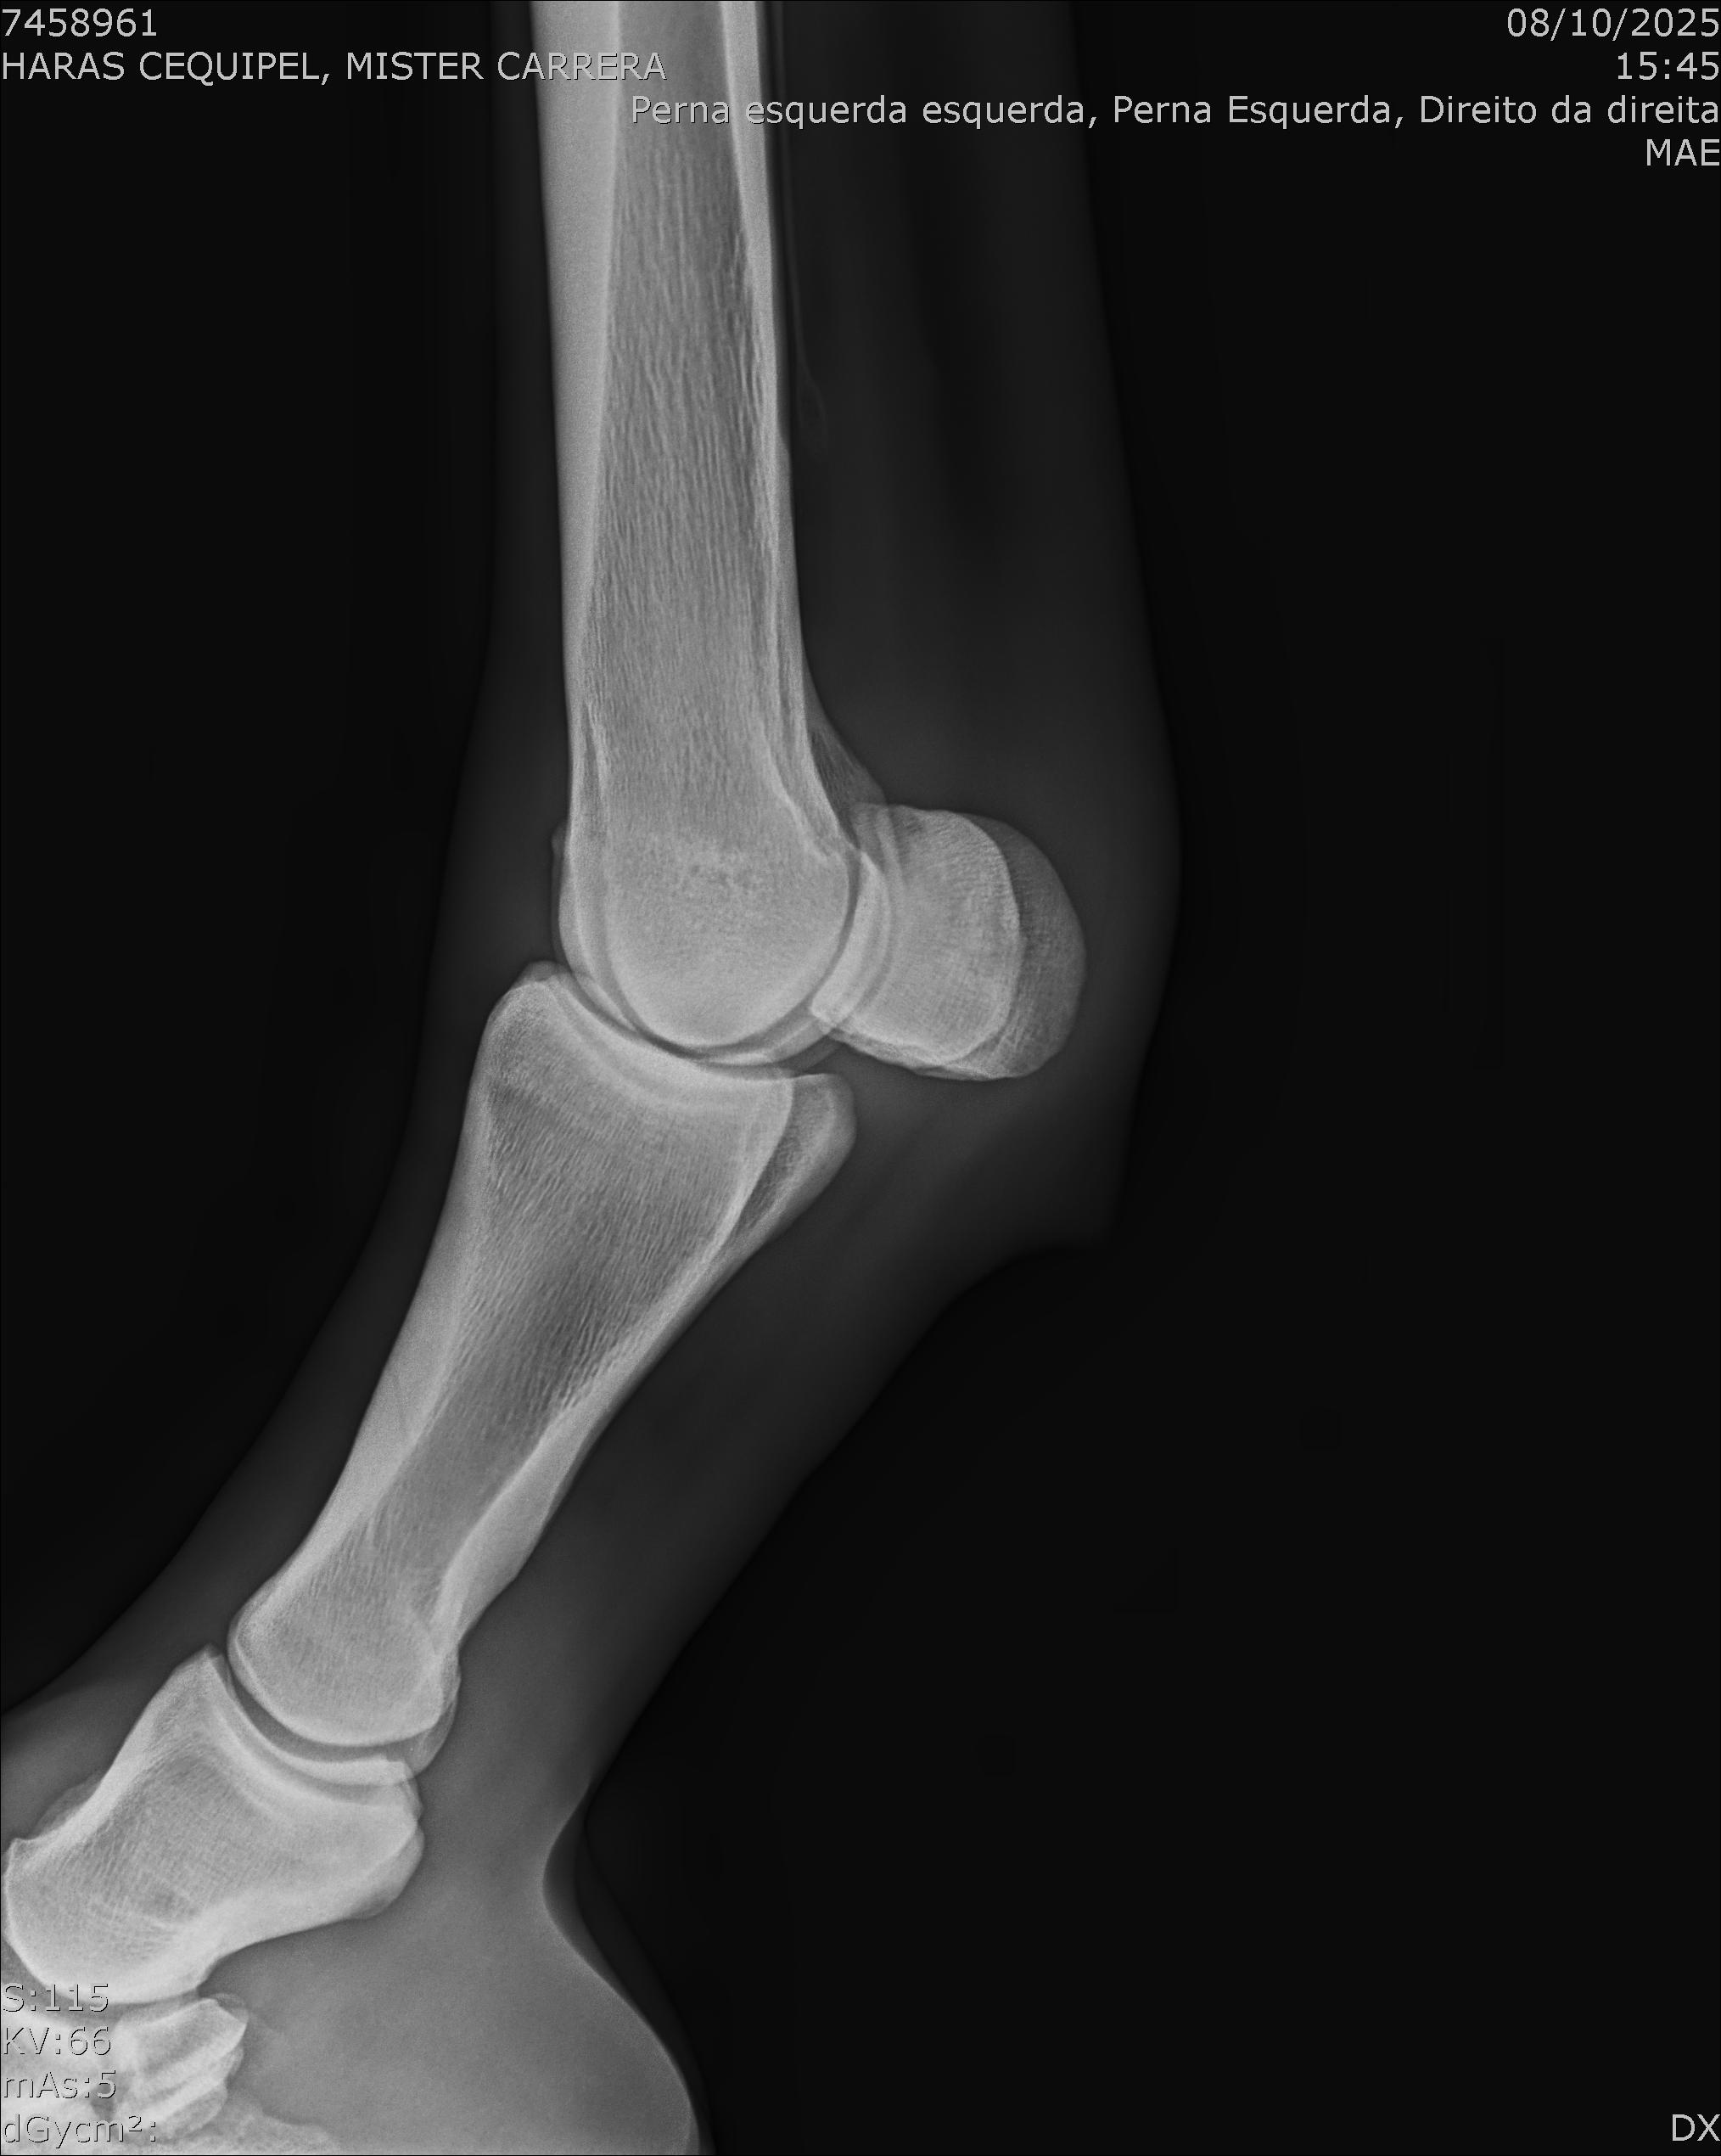

:: RAIOS-X DO LOTE